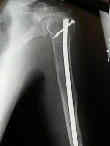

Se localiza, preferentemente, en los huesos donde existe médula ósea roja: vértebras, costillas, esternón, pelvis, cráneo y huesos largos (tercio proximal fémur y húmero).

Las fracturas patológicas de columna o fémur pueden ser el primer

síntoma. Se producen con un traumatismo mínimo o incluso sin trauma.

Radiográficos:

Las radiografías normales pueden mostrar osteopenia difusa.

"Lesiones perforadas" o en "sacabocado" sin ninguna formación de nuevo-hueso circundante. Su diámetro es variable (hasta 5 cm.), redondas y múltiples.

Con el tiempo las lesiones pueden cambiar de osteopenia difusa a más permeativa con patrón destructivo apolillado, y a veces con expansión cortical.

La destrucción del hueso ocurre con poca o ninguna formación de hueso reactivo a menos que haya una fractura patológica.

Fijación

quirúrgica:

El enclavado IM femoral profiláctico: